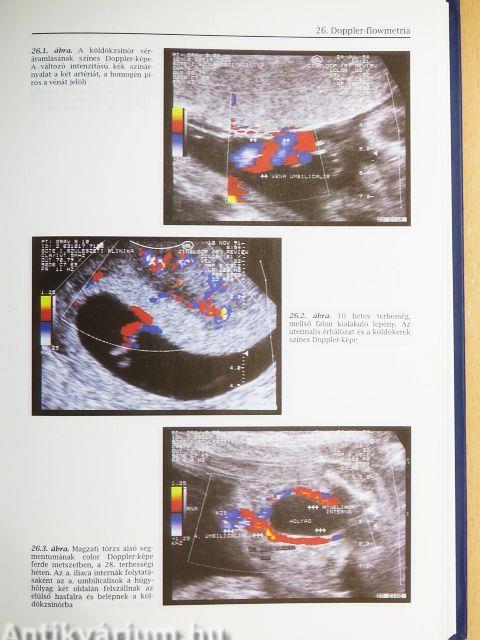

| Doppler-flowmetria (Szabó István és Papp Zoltán) | 277 |